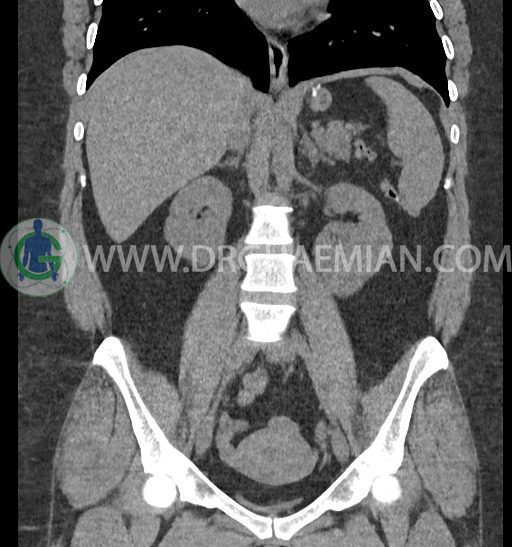

سی تی اسکن شکم و لگن با استفاده از اشعات ایکس تصاویر عرضی از ناحیه شکم و لگن ایجاد میکند. در این کیس کلیه نعل اسبی و سنگ کلیه مشاهده می شود.

در سی تی اسکن اسپیرال شکم و لگن بدون کنتراست (مولتی دیدکتور 16 با مقاطع ظریف و بازسازی های ساژیتال و کرونال) :

-horseshoe kidney

-حداقل سه سنگ 5mm در کلیه راست و یک سنگ 3mm در کلیه چپ بدون شواهدی از هیدرونفروز

ضایعهای در کبد، کیسه صفرا، مجاری صفراوی، طحال، پانکراس و آدرنالها مشهود نیست.

لنف آدنوپاتی در اطراف آئورت و IVC دیده نمیشود.

مایع آزاد در حفره شکم و لگن رویت نمی شود.